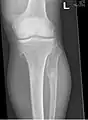

The diagnosis of HMO is based upon establishing an accurate correlation between the above-mentioned clinical features and the characteristic radiographic features. Family history can provide an important clue to the diagnosis. This is supplemented by testing for the two genes in which pathogenic variants are known to cause HMO namely EXT1 and EXT2. A combination of sequence analysis and deletion analysis of the entire coding regions of both EXT1 and EXT2 detects pathogenic variants in 70–95% of affected individuals.[3][4] The hallmark of radiographic diagnosis is the presence of osteochondromas at the metaphyseal ends of long bones in which the cortex and medulla of the osteochondroma represent a continuous extension of the host bone. This is readily demonstrable in radiographs of the knees.[3][1]

multiple osteochondromas around the knee

It is characterized by the growth of cartilage-capped benign bone tumours around areas of active bone growth, particularly the metaphysis of the long bones. Typically five or six exostoses are found in upper and lower limbs. Image depicts adult regrowth after knee replacement.